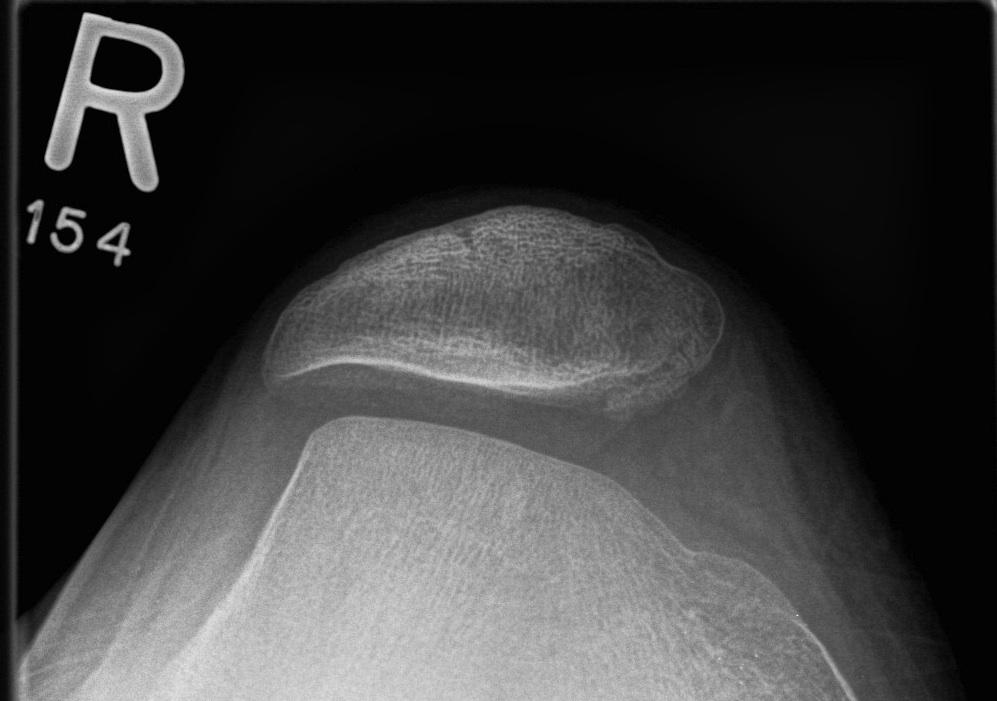

2. Assess Trochlea Dysplasia

Dejour Crossover Sign

- lateral x-ray at 30o with condyles superimposed

- identify base of trochlea

Normal

- clearly defined trochlea groove

Abnormal / Crossover

- line of floor of trochlea crosses lateral lip of condyle

- indicates trochlea is deficient proximally